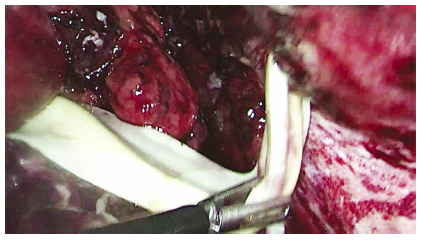

Se solicita una tomografía abdominal que revela una gran colección intraabdominal en el hemiabdomen derecho (Figura 1); se decide la laparoscopía exploratoria en la que se encuentra un absceso gigante intraabdominal de 750 cc (Figuras 2 y 3), que va desde el reborde inferior del hígado hasta el fondo de saco de Douglas. Se toma muestra para cultivo y se drena. Un útero aumentado de tamaño con fibrina en sus paredes, edema y eritema severo en la trompa derecha, revisando con azul de metileno para verificar su permeabilidad. Se encuentra el apéndice cecal en fase necrosada y perforada (Figura 4), el cual se extrae. Posteriormente se realiza el lavado peritoneal con 6.000 cc de solución salina normal (Figura 5). Se deja drenaje en fondo de saco de Douglas (Figura 6). El tiempo de hospitalización y el manejo antibiótico con piperacilina tazobactam fue de 10 días. El reporte del cultivo fue Escherichia coli.